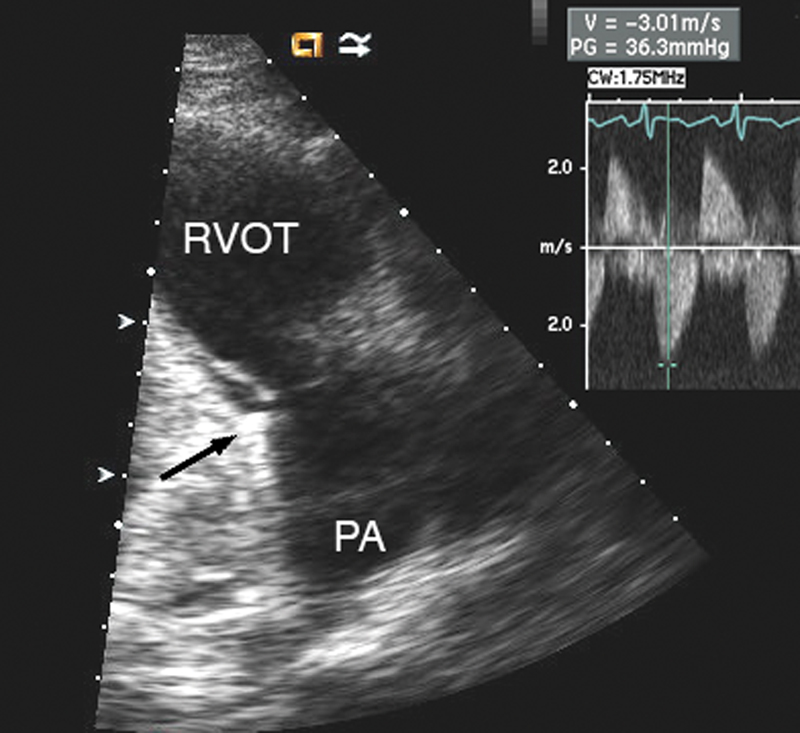

فحوصات تشخيصية لبعض امراض القلب والشرايين التاجية